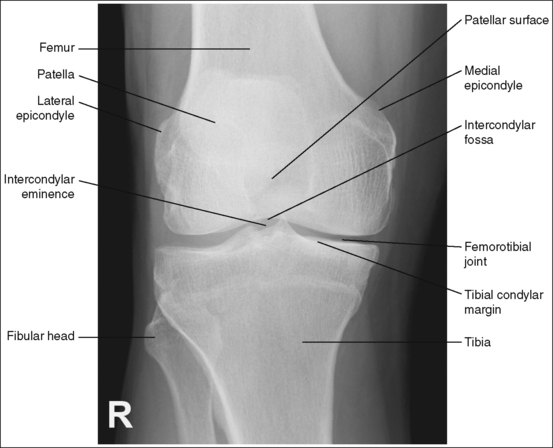

The knee demonstrates an AP projection. The medial and lateral femoral epicondyles are in profile, the femoral condyles are symmetrical, the intercondylar eminence is centered within the intercondylar fossa, and the tibia is superimposed over 0.25 inch (0.6 cm) of the fibular head.

• To obtain an AP knee projection, place the patient in a supine position with the knee fully extended. Internally rotate the leg until an imaginary line drawn between the medial and lateral femoral epicondyles is positioned parallel with the IR (Figure 6-71). This positioning places the medial and lateral femoral epicondyles at equal distances from the IR as well as medially and laterally in profile, respectively. It also centers the intercondylar eminence within the intercondylar fossa and draws the fibular neck and a portion of the fibular head from beneath the tibia.

• Effect of rotation. If the femoral epicondyles are not positioned parallel with the IR, an AP projection has not been obtained. If the patient's leg was not internally rotated enough to place the epicondyles at equal distances from the IR, they are not in profile, the medial femoral condyle appears larger than the lateral condyle, and the tibia is superimposed over more than 0.25 inch (0.6 cm) of the fibular head (see Image 54). If the patient's leg was internally rotated more than needed to place the femoral epicondyles at equal distances from the IR, the epicondyles are not demonstrated in profile, the lateral femoral condyle appears larger than the medial condyle, and the tibia is superimposed over less than 0.25 inch (0.6 cm) of the fibular head (see Image 55).

The knee joint space is open, the anterior and posterior condylar margins of the tibia are superimposed, the intercondylar eminence and tubercles are demonstrated in profile, and the fibular head is demonstrated approximately 0.5 inch (1.25 cm) distal to the tibial plateau.

• The anterior and posterior condylar margins of the tibia are superimposed if the correct central ray angulation, as determined by the patient's upper thigh and buttocks thickness, is used. By studying the tibial plateau region, you will see that the tibial plateau slopes distally approximately 5 degrees from the anterior condylar margin to the posterior condylar margin on both the medial and lateral aspects (Figure 6-72). Only if the central ray is aligned parallel with the tibial plateau slope is an open knee joint space obtained.

• Determining the central ray angulation. When a patient is placed in a supine position, the degree and direction of the central ray angulation required depend on the thickness of the patient's upper thigh and buttocks. This thickness determines how the lower leg and the tibial plateau align with the IR. Figure 6-73 shows a guideline that can be used to determine the central ray angulation for different body sizes; it illustrates the relationship of the tibial plateau to the imaging table as the patient's upper thigh thickness increases. Note that a decrease occurs in femoral decline, and a shift occurs in the direction of the tibial plateau slope as the thickness of the thigh decreases. Because of this plateau shift, the central ray angulation must also be adjusted to keep it parallel with the plateau and to achieve an open knee joint. For optimal AP knee projections, measure from the patient's anterior superior iliac spine (ASIS) to the imaging table on either side to determine the central ray angulation to use for each knee examination. When measuring this distance, do not include the patient's abdominal tissue. Keep the calipers situated laterally next to the ASIS. If the measurement is less than 18 cm, a 5-degree caudal angle should be used. If the measurement is 19 to 24 cm, a perpendicular beam should be used. If the measurement is greater than 24 cm, a 5-degree cephalad angle should be used. Using the correct central ray angulation not only results in an open knee joint space but also provides optimal demonstration of the intercondylar eminence and tubercles without foreshortening.

• Analysis of joint space narrowing. On an AP knee projection with adequate positioning, joint space narrowing is evaluated by measuring the medial and lateral aspects of the knee joint, which are also referred to as compartments. The measurement of each of these compartments is obtained by determining the distance between the most distal femoral condylar surface and the posterior condylar margin of the tibia on each side. Comparison of these measurements with each other, with measurements from previous images, or with measurements of the other knee determines joint space narrowing or a valgus or varus deformity. In a valgus deformity the lateral compartment is narrower than the medial compartment; in a varus deformity the medial compartment is narrower (see Images 56 and 57). Precise measurements of the compartments are necessary to ensure early detection of joint space narrowing and are best obtained when the knee joint space is completely open. If an inaccurate central ray angulation was used for an AP knee projection, the knee joint is narrowed or obscured, the intercondylar eminence and tubercles are foreshortened, and the tibial plateau is demonstrated.

The patella lies just superior to the patellar surface of the femur and is situated slightly lateral to the knee midline. The intercondylar fossa is partially demonstrated.

• The position of the patella and the degree of intercondylar fossa demonstration are determined by the amount of knee flexion. To visualize the patella and fossa as required, the leg must be in full extension. As the knee is flexed, the patella shifts distally and medially onto the patellar surface of the femur and then laterally into the intercondylar fossa, duplicating a C-shaped path that is open laterally (Figure 6-74). Thus, the patella is demonstrated at different locations, depending on the degree of knee flexion. Generally, when the knee is flexed 20 degrees, the patella is demonstrated on the patellar surface. With 30 to 70 degrees of knee flexion, the patella is demonstrated between the patellar surface and the intercondylar fossa. At 90 degrees to full knee flexion, the patella is demonstrated within the intercondylar fossa.

• Center the central ray to the midline of the knee at a level 1 inch (2.5 cm) distal to the palpable medial epicondyle to place the knee joint in the center of the exposure field. (As long as the knee remains extended, an alternative central ray placement is 0.5 inch (1.25 cm) distal to the patellar apex.) Open the longitudinal collimation enough to include one fourth of the distal femur and proximal lower leg. Transverse collimation should be to within 0.5 inch (1.25 cm) of the knee skin line.